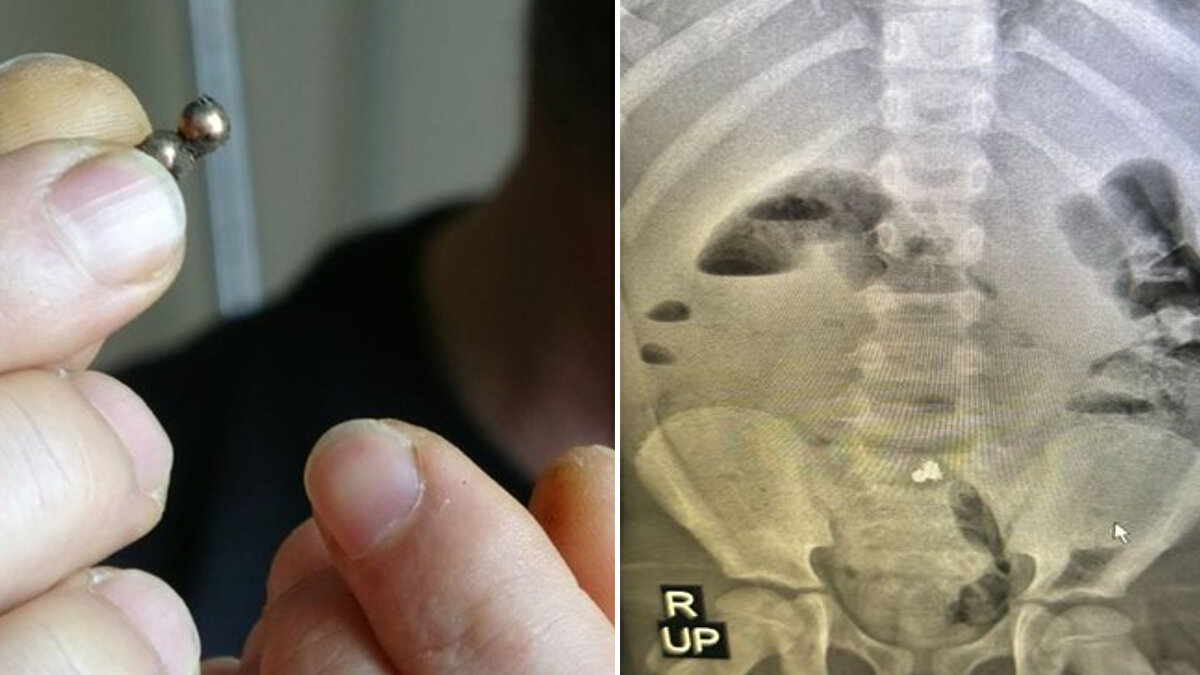

Çekilen röntgende bağırsağına yapışmış 3 parça mıknatıs tespit edilen çocuğun ameliyatına karar verildi.

Cerrahi Tıp Bilimleri Bölümü Çocuk Cerrahisi Anabilim Dalı Dr. Öğr. Üyesi Halil İbrahim Çakmak ve ekibi tarafından gerçekleştirilen operasyonla mıknatıslar çıkarılarak Miraç'ın üç yerden delinen bağırsağı dikildi.